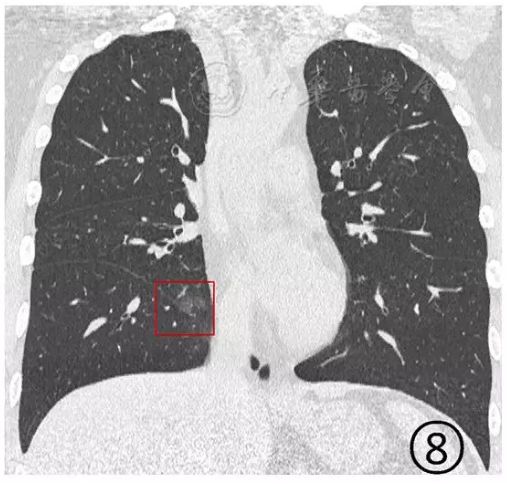

下面这个新冠肺炎患者,磨玻璃阴影内有细小的网格状阴影,图片清晰度略差,用意念看看,如果在电脑上把图像放大了看,可能就一清二楚了。

图8